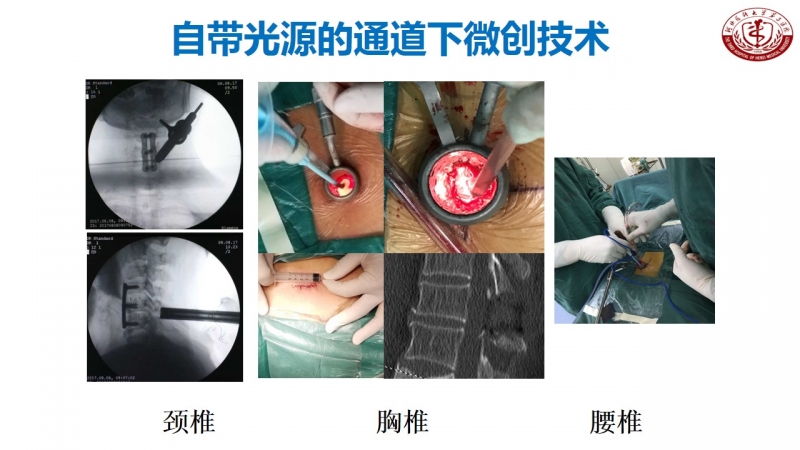

其实,在河北医科大学第三医院脊柱外科不乏这样的新技术创新。丁文元教授从医33年来,在脊柱疾病相关基础临床研究和治疗中做了大量的工作。

科室发展,未来可期

脊柱外科目前所开展的诊疗技术(滑动查看)

相信河北医科大学第三医院脊柱外科在新的学科带头人的领导下,不忘初心,砥砺前行,做好脊柱基础及临床研究,逐步提高学术影响力,攻克临床上各个难关,提升临床诊疗水平,使脊柱外科朝着精准化、微创化、显微化、智能化发展,造福更多患者。